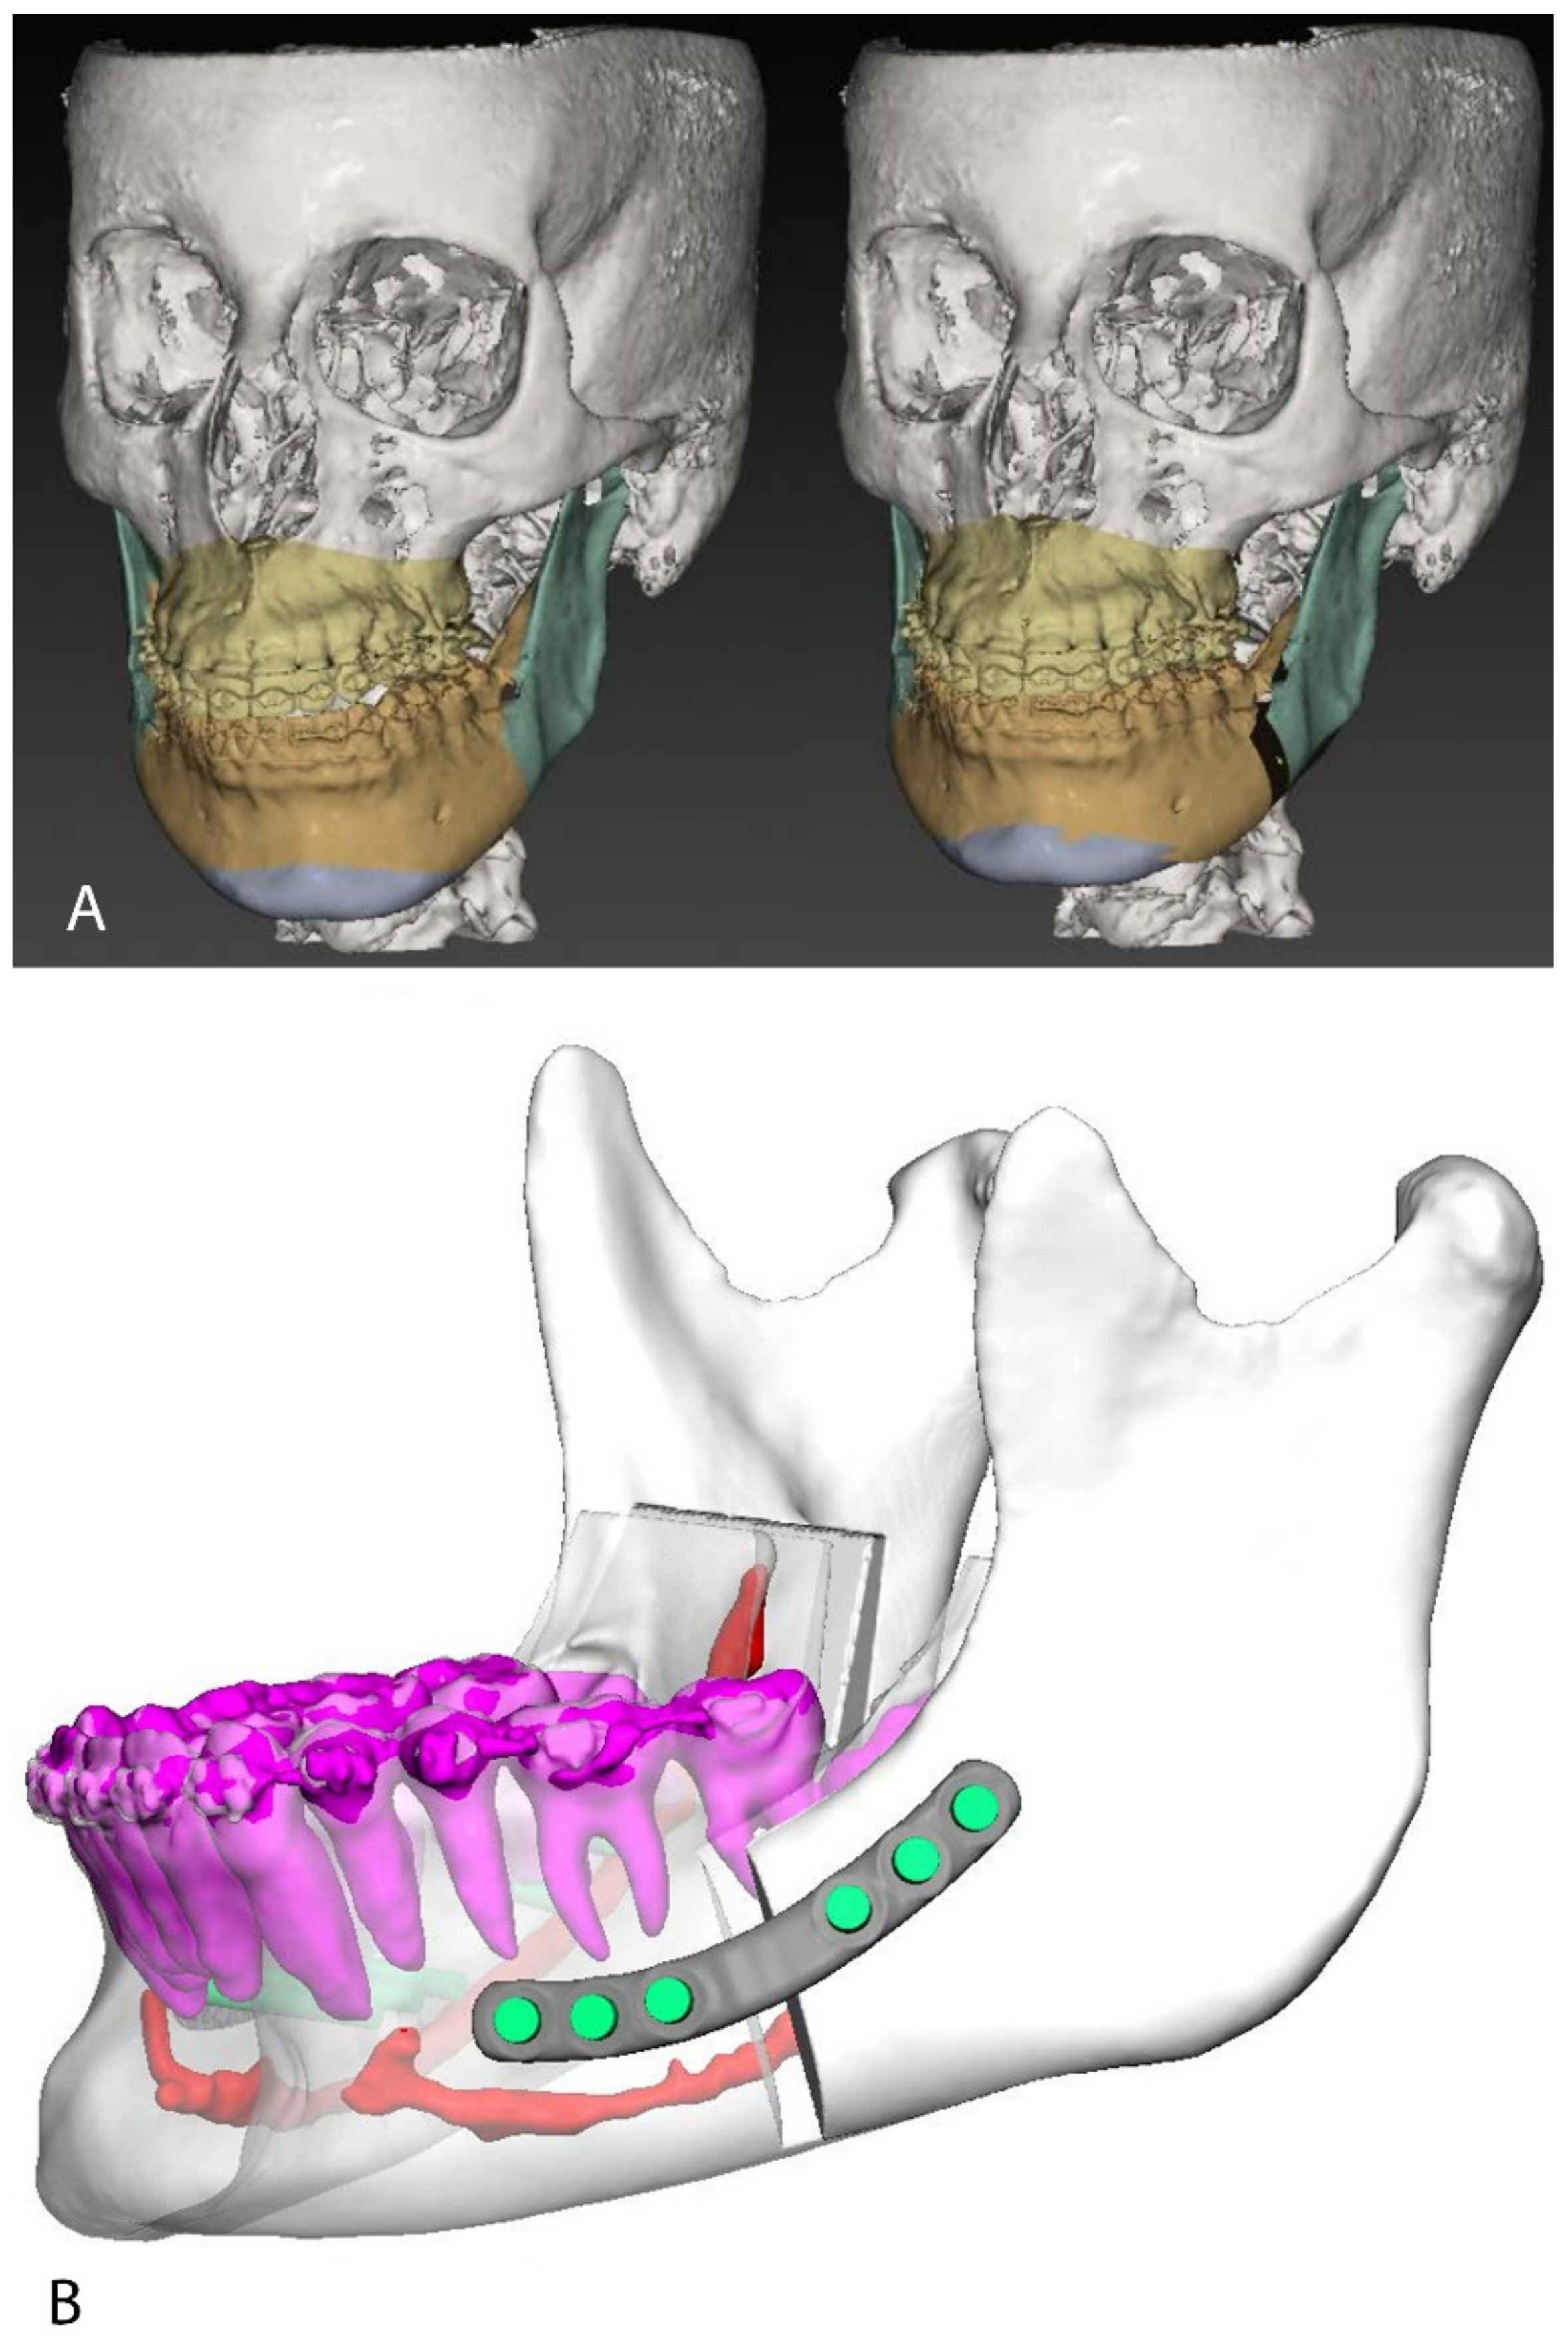

2.1. Case Planning and Surgery